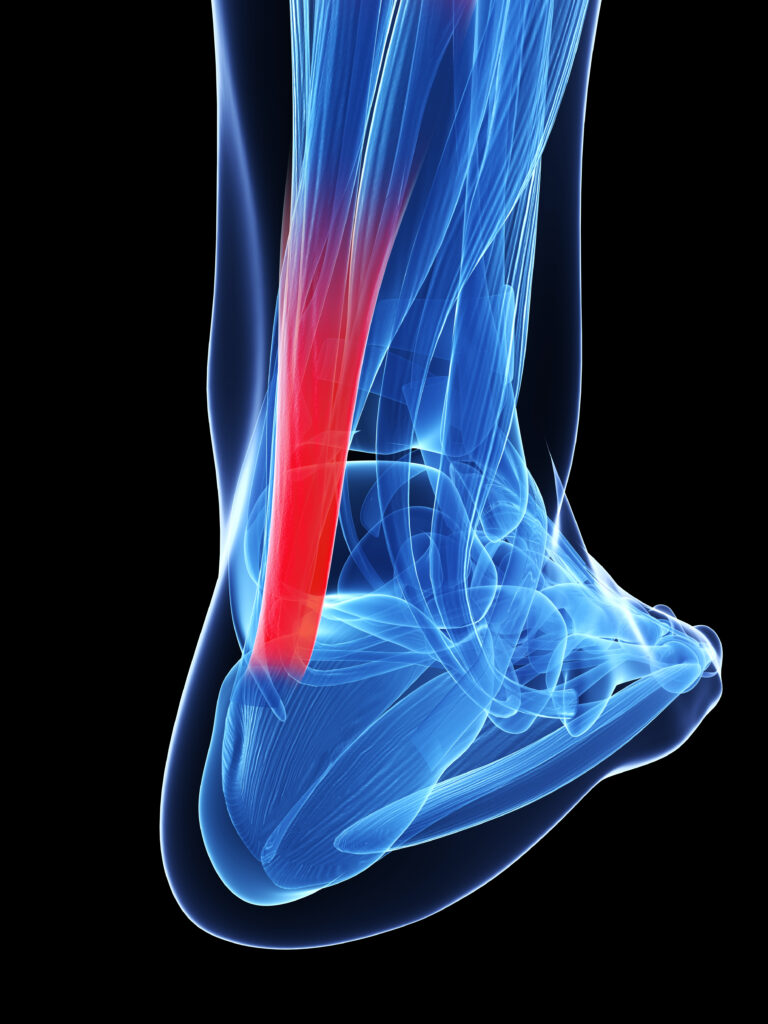

Achilles Tendon Partial Tear Symptoms: What to Expect

Achilles Tendons don’t always completely tear, sometimes they partially tear. Typically, this occurs from a strong contraction of the calf muscle overstressing the tendon. While the symptoms are less obvious compared to a complete tear, many of the symptoms are similar. Walking becomes more difficult. The leg can swell around the tendon. The calf can […]